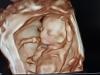

У знакомой девочки из Кулакова такая красивая фотка в 4д еще с 12 недель. Я тоже захотела, пошла в инвитро и получилось вот это «тесто» как у всех😅😅 малышка моя не хотела поворачиваться лицом. Но смотреть было интереснее, чем обычное узи. Думаю вот теперь, может второй скрининг в Кулакова пройти)

@dmitrovakarina1, вот может в Кулакова какие-то супер аппараты)) там реально фотки красивые, я таких еще не видела

Они и в 19 как инопланетяне еще 😁 лучше 28+ делать )) я еще в 36 делала) так там булка такая ❤️

4д лучше 28-32. Муж может посмотреть на обычном узи, там хорошо видно очертание головы, конечностей

Смысла нет, все специалисты говорят в 28 недель делать ))

Да ну рано ещё. Недель 25 минимум